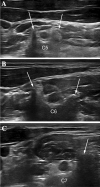

Axonal polyneuropathy is the main feature of hereditary transthyretin amyloidosis (ATTRv). Nerve morphological abnormalities have been reported, but longitudinal changes have never been assessed. We performed a prospective widespread nerve ultrasound evaluation and nerve cross-sectional area (CSA) was compared with baseline data in both ATTRv patients and pre-symptomatic carriers. Thirty-eight subjects were evaluated (mean follow-up 17.1 months), among them 21 had polyneuropathy while 17 were pre-symptomatic carriers. CSA significantly increased at brachial plexus in both groups (p = 0.008 and p = 0.012) pointing to progressive brachial plexus enlargement as a longitudinal biomarker of both disease progression and disease occurrence in pre-symptomatic carriers.